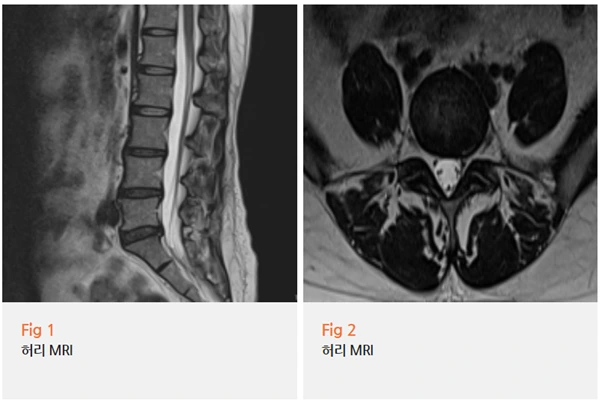

그리고 결과를 확인했을 때 예상대로였습니다.

%EA%B7%B8%EB%A6%BC16.png?type=w966

추간판 탈출증, 즉 허리디스크가 명확하게 보였고

이게 신경근을 압박하고 있었습니다.